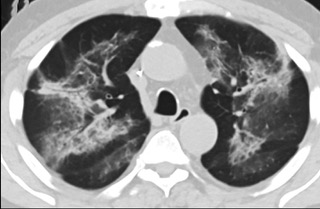

疑點(diǎn)二,中國(guó)科研工作者從60篇研究論文中篩選出142位電子煙肺炎患者的250張影像圖片,邀請(qǐng)3位放射科權(quán)威專家,對(duì)上述全部影像圖片、相關(guān)病人臨床信息以及文獻(xiàn)原文進(jìn)行了仔細(xì)全面研究與審查,又有了新的發(fā)現(xiàn)。

6天后的軸向CT平掃圖像顯示毛玻璃影變?yōu)閷?shí)變和輕度結(jié)構(gòu)扭曲。(同一病人CT影像)

16位被文獻(xiàn)報(bào)道為電子煙肺炎的患者被專家判定為“病毒性感染”,即有可能是新冠肺炎的“疑診患者”,其中更有5位臨床癥狀和治療情況相對(duì)完整的患者被判定為“中度可疑”。因此在2019年美國(guó)報(bào)道的電子煙肺炎中存在病毒性感染的病例,而且不排除美國(guó)電子煙肺炎中存在新冠肺炎的可能性。